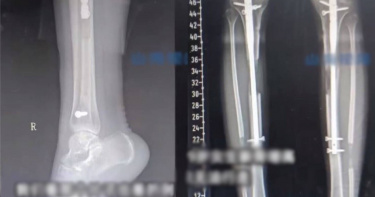

中國江蘇省1名女子2021年時花費60萬人民幣,至土耳其接受「斷骨增高術」,沒想到術後她的雙腿持續疼痛,不僅無法奔跑與蹲下,還罹患慢性骨髓炎。該名女子希望走法律途徑維護自身權益,不過由於她是跨國接受手術,因此想在中國立案困難重重。2021年中國江蘇省1名女子小夢(化名),在網路平台看到關於斷骨增高術的相關貼文,由於進行該手術在中國屬於違法行為,因此她透過貼文發佈者梁姓男子的介紹加入微信群組,群組內持續有人分享到土耳其進行無外架內置手術的案例。根據中國當地媒體報導,小夢花費了60萬人民幣,在2021年5月飛往土耳其,分2次完成大腿內置與小腿外架手術,怎料術後第6個月小夢右小腿斷骨處出現紅腫潰爛,最終被診斷為急性骨髓炎。當時她住在土耳其醫院安排的飯店裡,甚至受到梁姓男子威脅,稱其只有在微信群組裡說好話,才能接受後續治療。然而土耳其當地醫生並未對小夢執行清創,與取出她體內的髓內釘,而是只開立口服抗生素,最終導致小夢病情惡化成慢性骨髓炎。小夢告訴中國當地媒體,她體內的髓內釘讓她無法接受核磁共振檢查,也因為取出釘子的手術存在高風險,可能引發二次骨折,因此至今仍未取出。小夢後續在中國接受X型腿矯正手術,但效果並不理想。小夢坦言「我的腿經常酸痛,長時間走路就會感到疲勞和僵硬。斷骨處也很痛,我不能像正常人一樣起立、蹲下」。更令小夢氣憤的是,她的經歷竟然被不肖醫療仲介當作反面教材,「他們說我是因為做了內置和外架結合的手術才這樣的,現在他們都在推銷全內置手術。」與小夢同期前往土耳其接受手術的患者,也有不少人出現後遺症,其中1名女子小何(化名),因首次手術的內置針被誤植成X型,導致骨骼延長失敗,後續更因此接受4次修復手術。起初醫院承諾補償小何2個月的住宿費,沒想到卻在事後反悔,提出改成用拉人頭的方式抵償,小何每介紹1人做手術,就可獲得1000美元的報酬。該醫療機構的提議受到小何拒絕後,竟在深夜派人闖入小何住處向她索討費用,該衝突最終在警方當場後才得以平息。另一名患者西西(化名),本來沒有增高需求,卻被醫療仲介的話術誘導,前往土耳其進行手術。西西表示「他們把這個手術說的就像割雙眼皮一樣簡單,承諾術後可無痛恢復運動能力」沒想到真實的術後生活,卻是每天都需要注射止痛針緩解疼痛。西西甚至在術後1年,發現骨骼未完全癒合,還因此讓下肢變成X型腿。小夢向中國當地媒體指出,術前微信群組規模龐大,總共有十幾個群,從小夢提供的聊天紀錄截圖可以看到,該機構聲稱3個月內以為100多位中國人進行斷骨增高術。小夢還透露,她後來得知當初介紹她進行手術的梁男原本是土耳其某醫療機構在中國的下線,後來自立門戶。他在2024年8月被曝光與中國山東省荷澤市某民營醫院合作進行違法手術,該合作醫生被吊銷醫師執照。小夢還補充道「據我了解,他們目前已經轉移到新疆烏魯木齊,單台手術報價50萬元,拉1個人給8萬元介紹費」對此南京醫科大學第二附屬醫院骨科副主任醫師王伯堯表示,目前中國明令禁止以美容為目的進行肢體延長手術,其合法用途僅限正畸矯形。王伯堯也指出,髓內釘可能引起髓腔發炎,患者還可能面臨感染、骨癒合障礙,以及神經不可逆損傷等併發症。小夢希望藉由法律維護自身權益,然而她的付款紀錄與病例都在土耳其,因此想在中國立案相當困難。中國知名律師付建指出,小夢可以聯繫土耳其當地律師,以獲取醫院和醫生的執業資格相關資訊,從而確認醫療行為的合法性,一旦發現該醫院不具備相關資格,或手術中醫師存在過失,小夢就能依照土耳其法律追究民事賠償責任。付建也提到,若醫療仲介和醫院共同隱瞞後遺症的真相,以詐欺手段誘導消費者進行手術,小夢可將醫療仲介列為共同被告。此外雖然該醫療事件發生於國外,但根據中國法律,如果當事人有共同經常居住地,則適用該地法律,因此本案還是有機會在中國立案起訴。